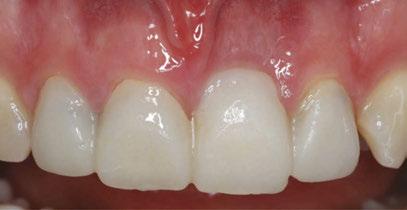

Following PATZi, anterior support was sought next. As such, the nasal mucosa was elevated to expose the floor of the nasal cavity and the bone of the inferior conchae. A pair of 25 mm transnasal implants were placed, and each achieved high insertion torque of 45+ Ncm (Figures 9-11). Continuing with the PATZi protocol and treatment plan, 42.5 mm long zygomatic implants were placed in both zygomas. The zygomatic implants were placed using an extrasinus approach and both achieved insertion torque of 45+Ncm. Buccal fat pedicles were advanced bilaterally to cover extrasinus portions of the zygomatic implants, and flap closure was achieved with 4-0 chromic gut suture. The patient was immediately temporized with a screw-retained transitional bridge (Figure 12), and a final zirconia restoration was delivered after 8 months of healing (Figure 13).